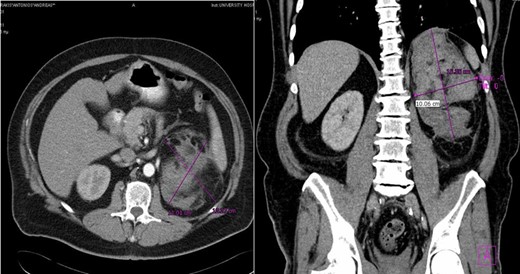

CASE REPORT 1

Case 1 presenting imaging (CT) showing a large left peri-adrenal hematoma.